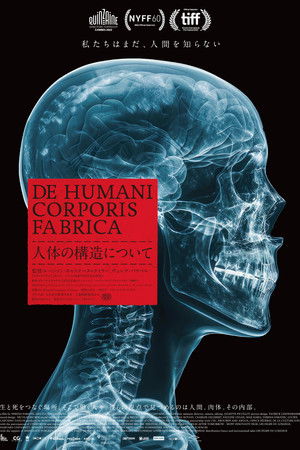

De humani corporis fabrica

(2023)Overview

An extraordinary adventure through the interior of the human body; or the discovery of an alien landscape of unprecedented beauty.

Original TitleDe humani corporis fabrica